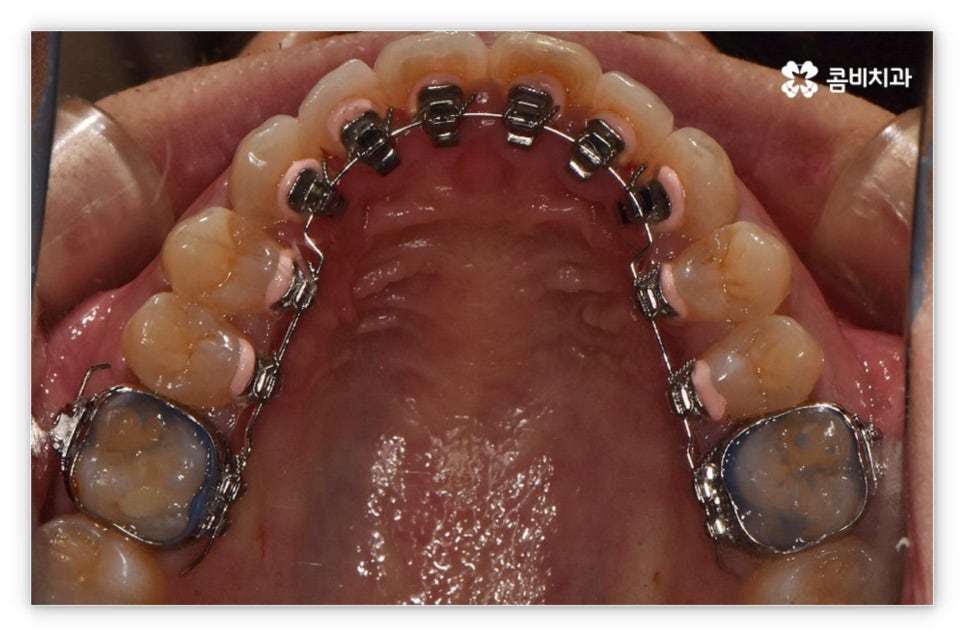

살펴본 바와 같이 앞니설측교정 의 장점에도 불구하고 아랫니 부분은 장치가 혀에 닿게 되기 때문에 환자분들께서 불편함을 느낄 수 있고 혹시라도 혀가 브라켓에 잘못 쓸리거나 눌렸을 때 통증이 발생할 수도 있으며 발음이 불분명해지는 문제가 생길 수 있는데요. 이러한 이유로 앞니설측교정 에 대해서 고민이 되시는 분들은 윗니 부분은 설측으로, 아랫니 부분은 일반 교정처럼 순측으로 진행하는 콤비 교정에 대해서 알아보시면 좋을 거예요. 위의 사진에서 살펴보실 수 있는 경우가 바로 이렇게 콤비 교정으로 진행한 환자분의 케이스인데 아랫니의 경우 보통 입술에 가려 별로 드러나지 않는 데다가 치아 색상인 세라믹 재질로 된 브라켓을 이용하기 때문에 설측 교정과 비교해도 심미성이 크게 떨어지지 않는다는 것을 알 수 있어요. 콤비 교정의 경우 설측 교정보다 비용적인 부담도 줄일 수 있으니 각 장치에 대한 장단점을 의료진분들과 충분히 상담하셔서 자신에게 맞는 장치를 선택하시면 좋을 거예요.